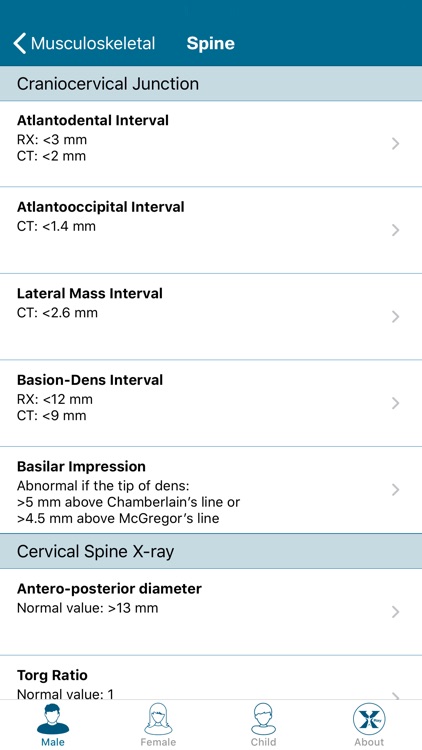

Created by radiologists for all those who practice medical imaging, this application constitutes an atlas of the main measurements in radiology and their normal values based on the most cited literature. It illustrates easy and reproducible methods using different imaging methods.

Created by radiologists for all those who practice medical imaging, this application constitutes an atlas of the main measurements in radiology and their normal values based on the most cited literature. It illustrates easy and reproducible methods using different imaging methods.

The application covers multiple imaging modalities: radiography, ultrasound, CT and MRI. The modules are divided into six sub-specialties: osteoarticular, cervical region, thorax, cardiovascular, abdomen and pelvis.